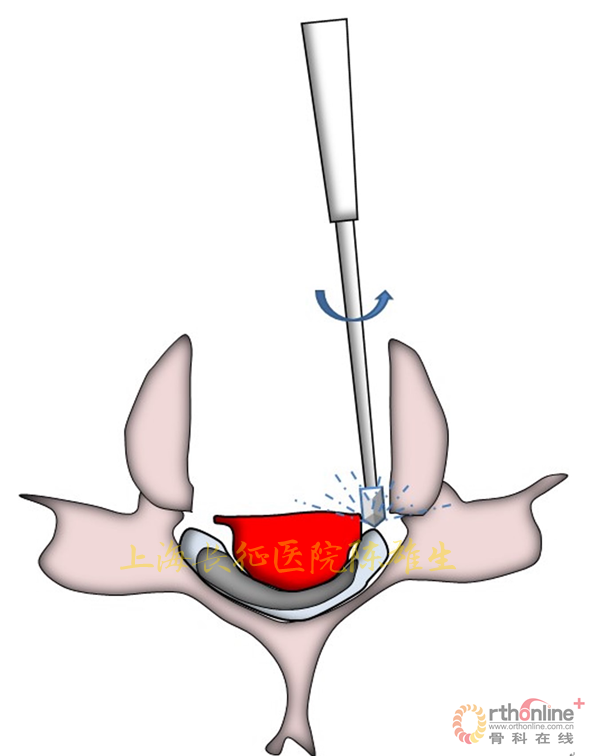

3.2.避免对受压迫的脊髓施加二次压迫

3.2.1磨钻切除椎体时保留椎体后壁

颈椎OPLL减压过程中,对骨化物稳定的把持非常重要。保留椎体后壁后用磨钻打磨骨化物相对较固定,减少磨钻打磨产生的震荡对脊髓的干扰;便于骨化物把持,保障操作过程不使骨化物塌陷压迫脊髓(图12)。

图12